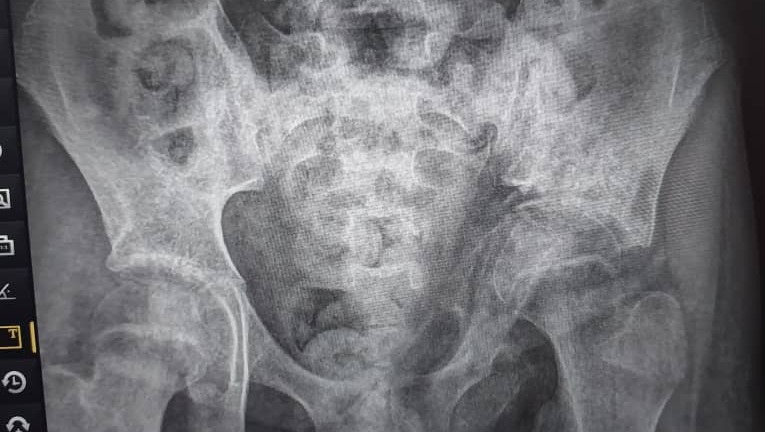

I am Luis Ojeda, Maury Mendoza's cousin. Maury and Rafael's 11-year-old little girl, Mariam, started feeling sick with headaches, dizziness, and fevers in April 2023. After multiple visits to the hospital and doing Exams, Lab Panels, and MRIs, Mariam was diagnosed with Non-Hodgkin Lymphoma of the bone, in her right acetabulum (hip socket).

While waiting for the biopsy, the symptoms worsened, the pain intensified, and it made it impossible for Mariam to walk. After a diagnosis of sarcoma (tumor in the tissue), uncertainty continued since it had to be confirmed with an immunohistochemical study (study of the tissue). That study revealed that the Lymphoma was in an advanced stage.